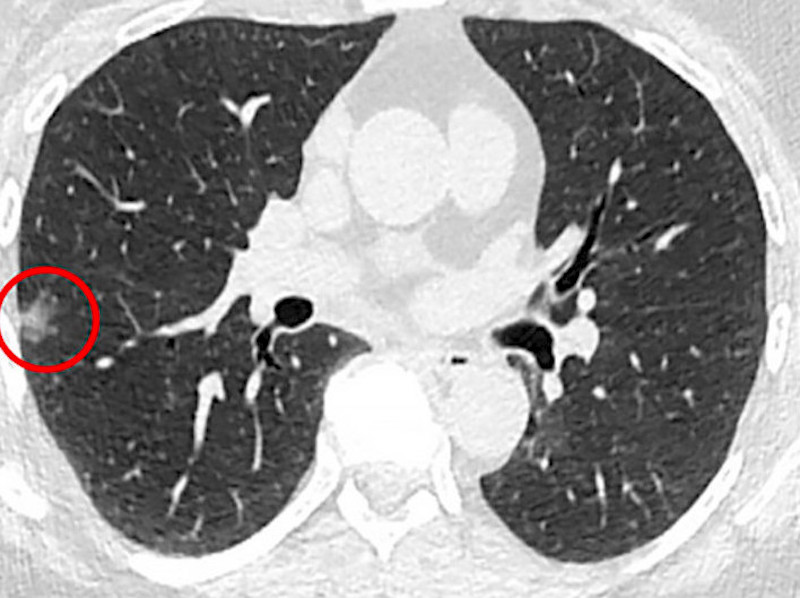

Scan of a patient in the Penn Medicine led-study with a lung nodule, circled in red. Credit: Penn Medicine.